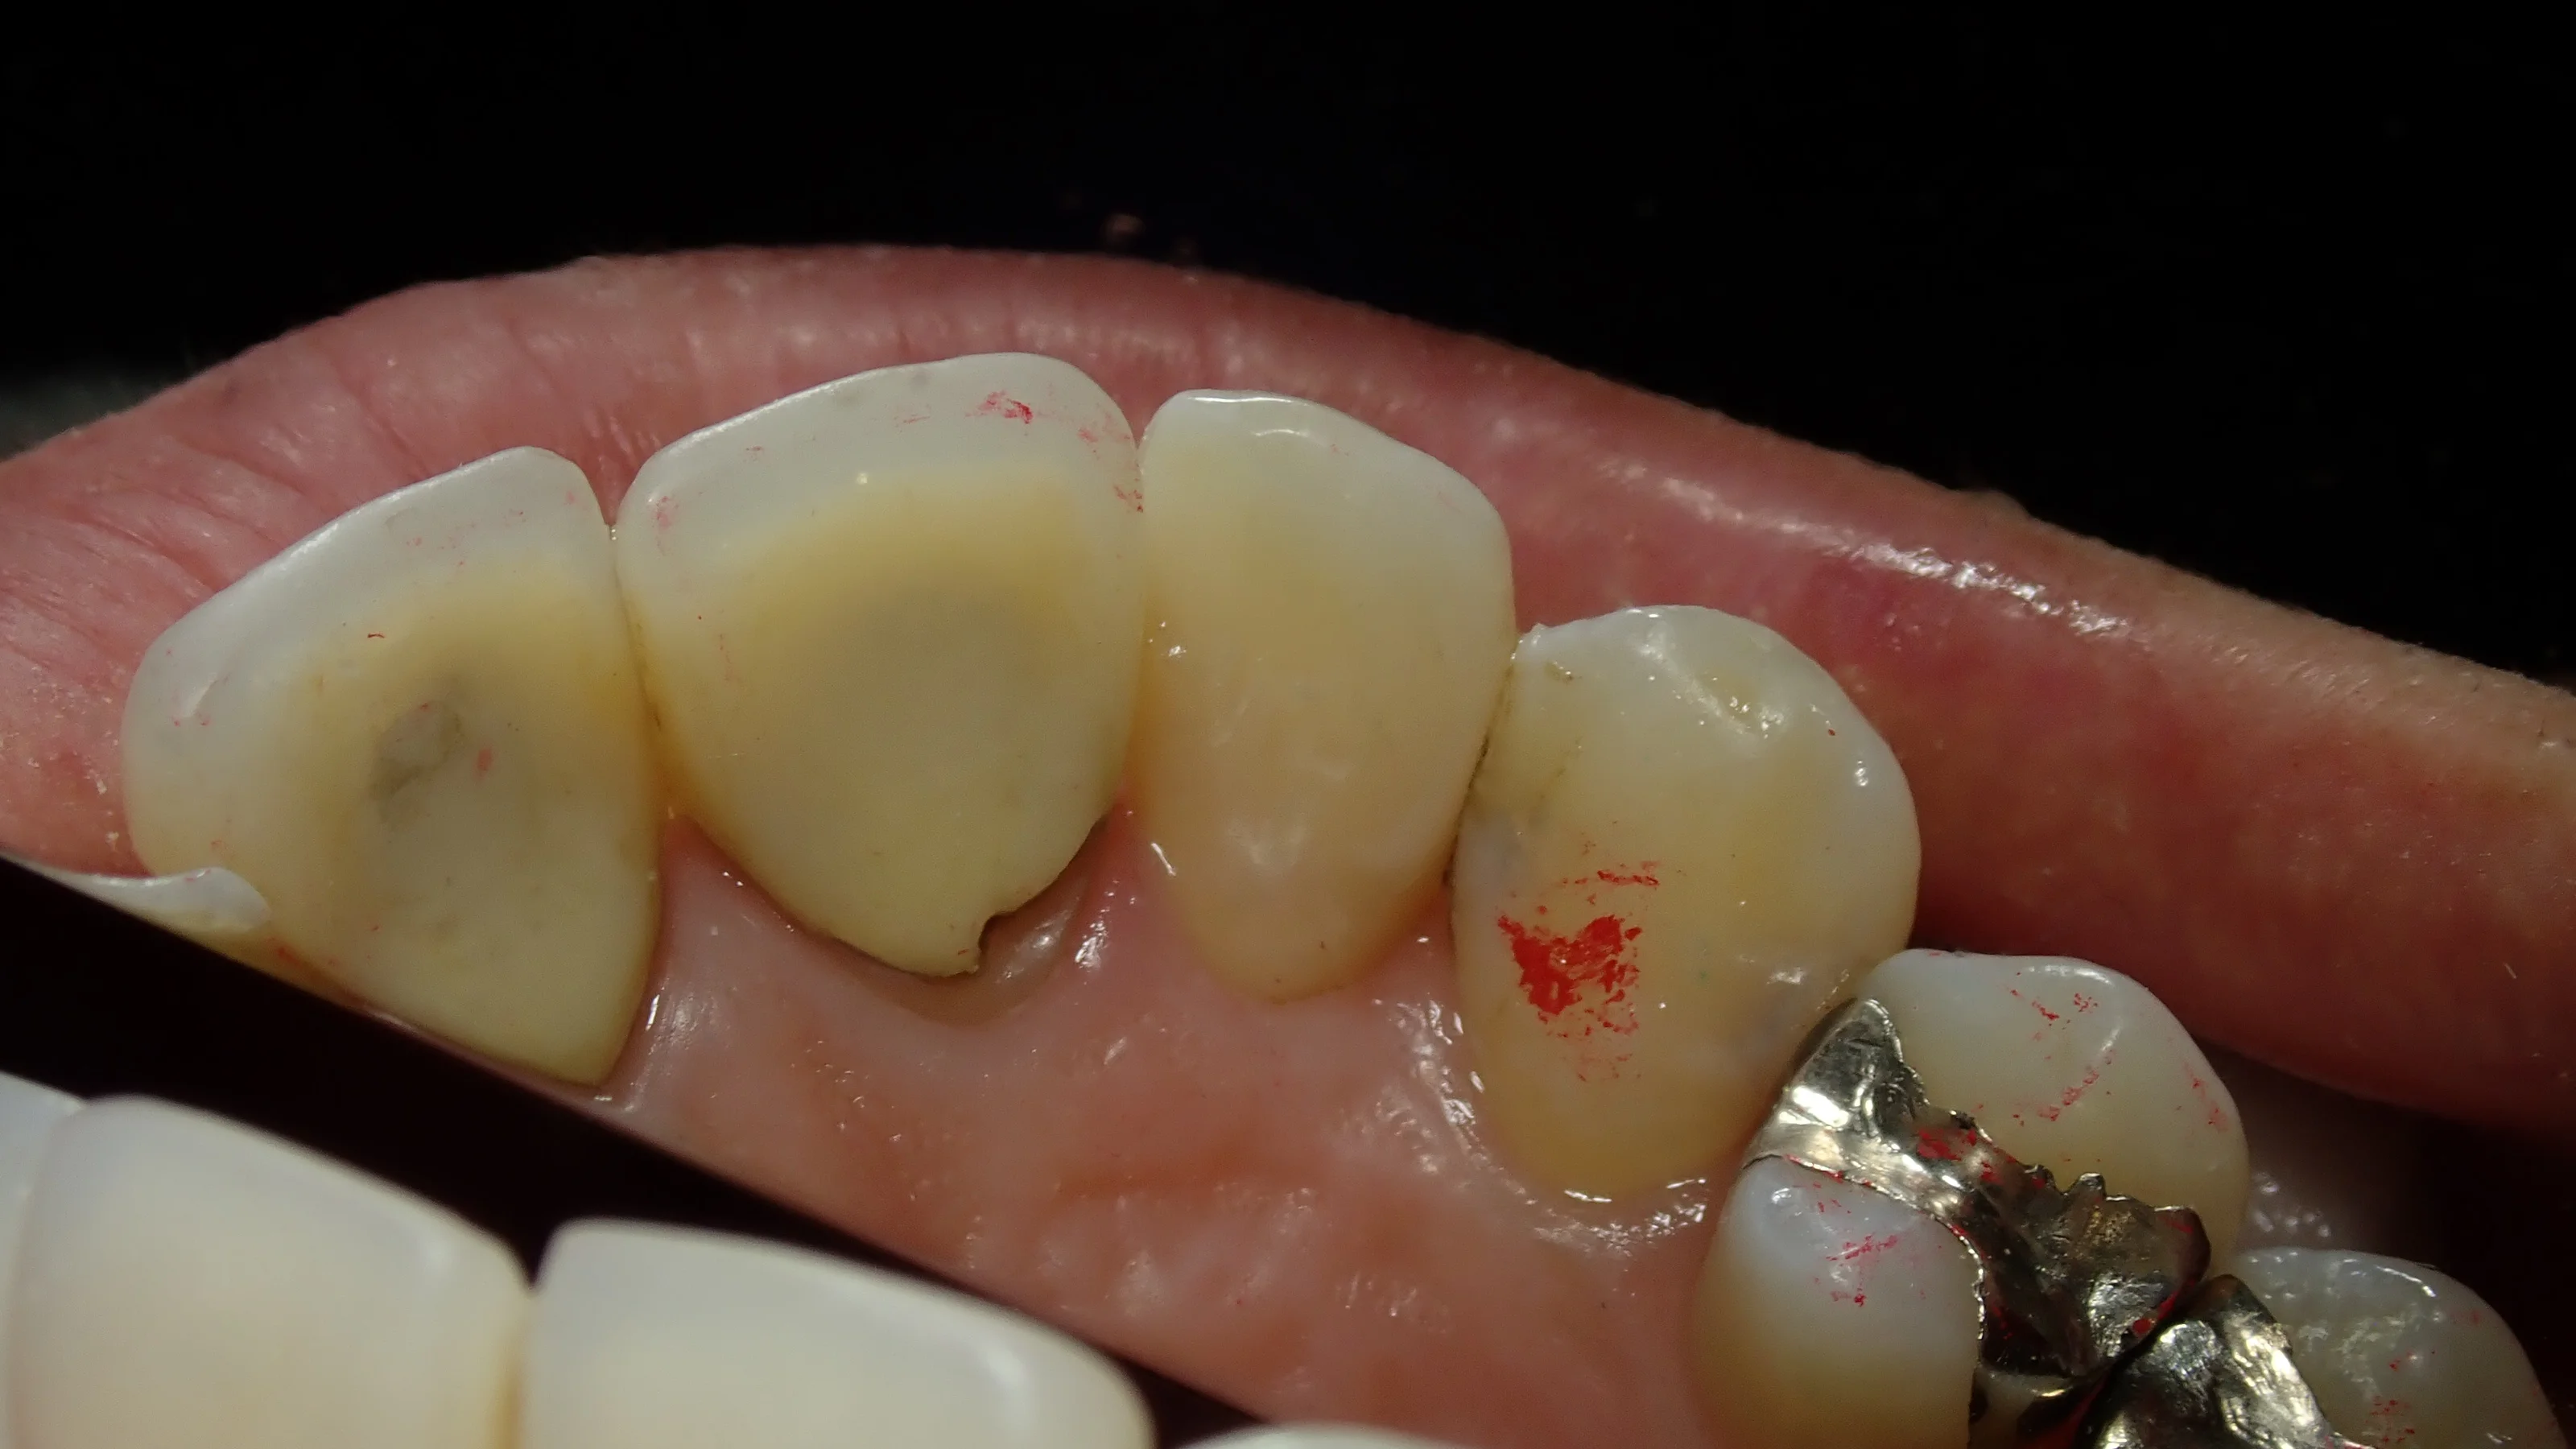

裏側がこんな感じです。

本来なら全周削って被せる「クラウン」形態になるような状況でしたが、無事に歯質を多く温存できたかと思います。